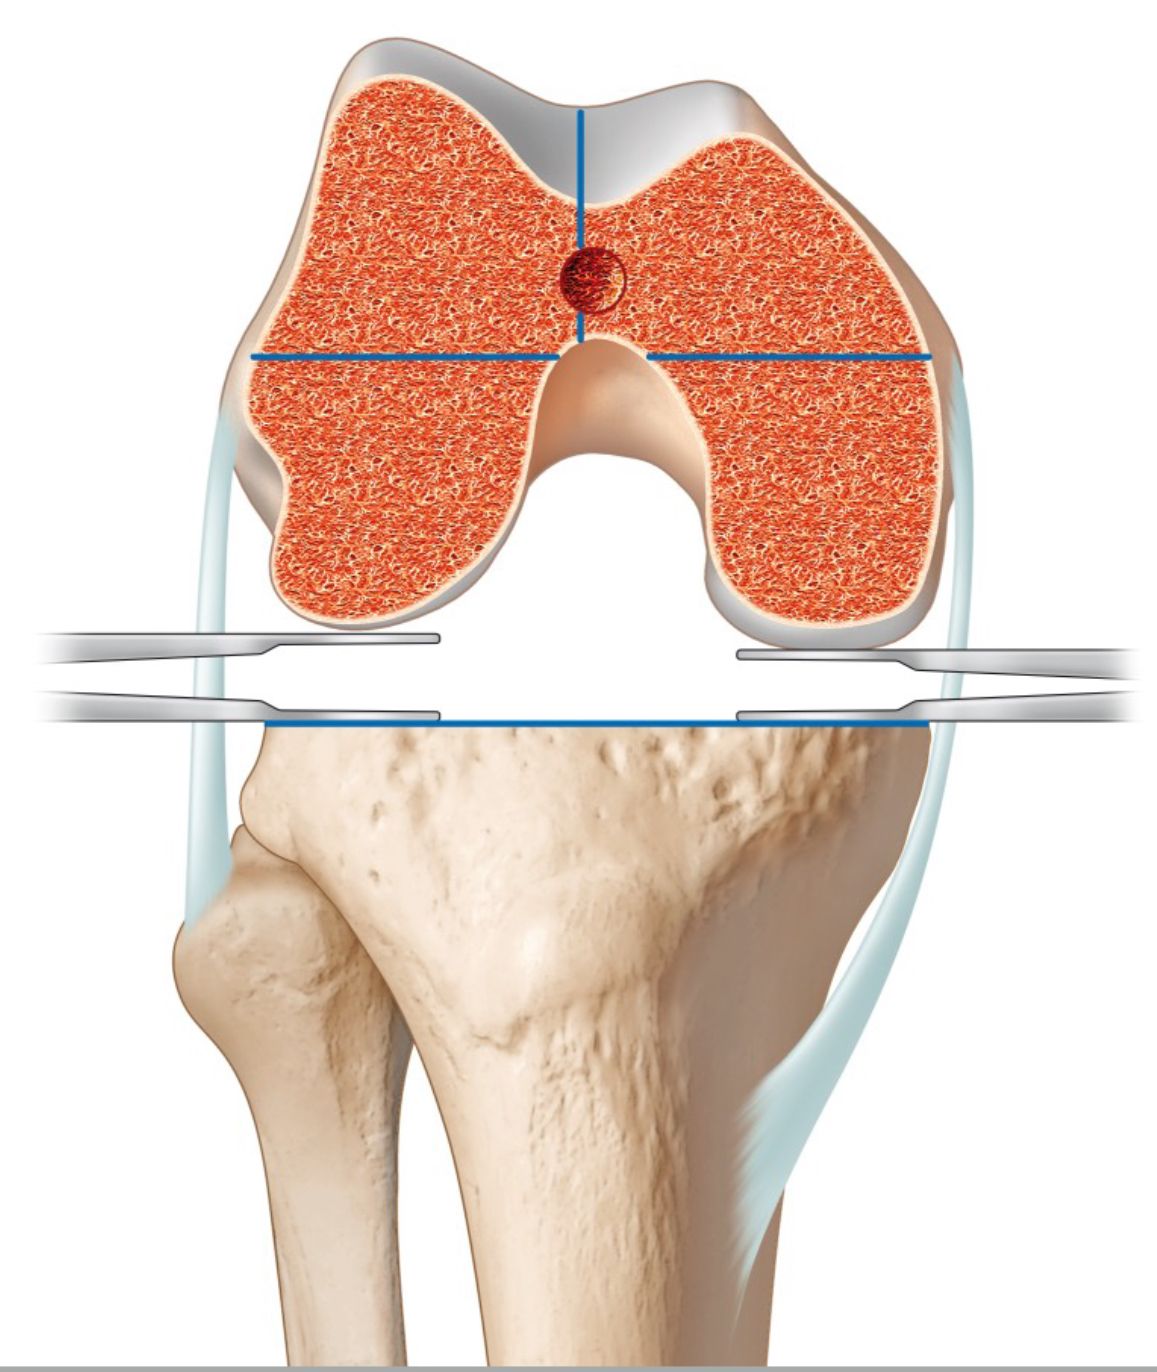

For every TKA we mark the tibia tubercle axis (TTA) of Insall and compare it with the anatomical centre of the proximal tibia using the mid-sulcus line (Fig 22 A and B).

The TTA should be max 5 mm or 25° external rotated to the mid-sulcus line in normal knees, and any proximal axial deformity of the tibia can be easily identified. For the tibia rotational alignment, we use two landmarks only. The TTA of Insall (functional landmark) and the “curve on curve” technique (anatomical landmark). When performing a medial pivoting knee, we combine the “floating technique” with the two landmarks to find the best rotational compromise to allow a lateral rollback in flexion without producing a patella lateralization in extension .

6. Basic biomechanics of tibia axial deformity and patella tracking

In the natural knee the TT is lateralized to the anatomical centre of the proximal tibia. The most common measurement of this ER positioning is the tibia-tubercle-trochlea groove (TT-TG) distance which on average is 7 mm and should be below 15 mm in normal knees [50]. This ER of the TT makes sense, since the natural knee has a screw home mechanism in full extension to lock the knee, which is driven by the medial condyle anatomy, menisci and both cruciate ligaments. After unlocking the knee during flexion, the tibia is internal rotating and beyond 60 ° of flexion the TT is under the trochlea of the femur with TT-TG 0 mm. In natural knees with patella dislocation, it could be shown that the TT-TG is significantly higher compared to normal knees [51]. During flexion the dynamic TT-TG is reduced, but never gets normal and in some patients, it is decompensating and gets even worse (Fig 20) [50]. This is the rational why in natural knees with pathological TT-TG more 15 mm, TT osteotomy with medialization is performed to bring the TT-TG back to normal and prevent patella maltracking or dislocation.

The complex screw home mechanism and self-rotational alignment of the natural knee during flexion cannot be reproduced with TKA implants. Only the bicruciate retaining/substituting and medial pivoting designs show some screw home mechanism whereas for all other TKA designs the TT-TG should be less than 5 mm in extension (tibia tubercle under the trochlea). This allows perfect patella tracking and brings the tibia component perpendicular to the TEA of the femur. In several biomechanical studies it could be shown that the rotational movements of all TKA designs during flexion are not natural, very variable and some of them even show paradoxical tibia external rotation [18]. Therefore, femorotibial mismatch in TKA between femur and tibia components during daily activities are common and remains a concern for bad function, early loosening and PE wear [16]. On the other hand, patellofemoral problems with maltracking and anterior knee pain are very common after TKA and the main cause is malrotation of the tibia and/or femur components [5, 10].

Without knowing all the details of this complex 3-D biomechanics of the patellofemoral joint, Insall has recommended to realign the prosthesis to the extensor mechanism during TKA surgery already 40 years ago. He introduced the tibia tubercle axis (TTA) for rotational alignment (Fig 21) which brings the TT under the trochlea from extension until deep flexion in all cases [1]. Most surgeons follow this simple technique but never thought about the wide variation of the TT to the proximal tibia anatomy. During the last decade several studies using 3-D imaging have shown that proximal tibia axial deformity is common in TKA patients and the TT position to the proximal tibia anatomy is very variable [22,30,48]--. Furthermore, it could be demonstrated that in varus knees external torsional deformities showed a clear correlation to the severity of the frontal malalignment [52]. The most commonly used measurement technique for knees with TKA is the anterior tibia tubercle angle (ATTA), which measures the angle between two lines (Fig 1 B and C) [4,30].

On average this angle is 25° with a wide range from 4 to 50°. 49% of knees show outliers > 5° and 15% more than 10°. Roughly 5° is equal to 1 mm, which correlates to the 5 mm of the TT-TG distance. Axial tibia component IR malalignment of more than 5° to the TT is clinically relevant [3].